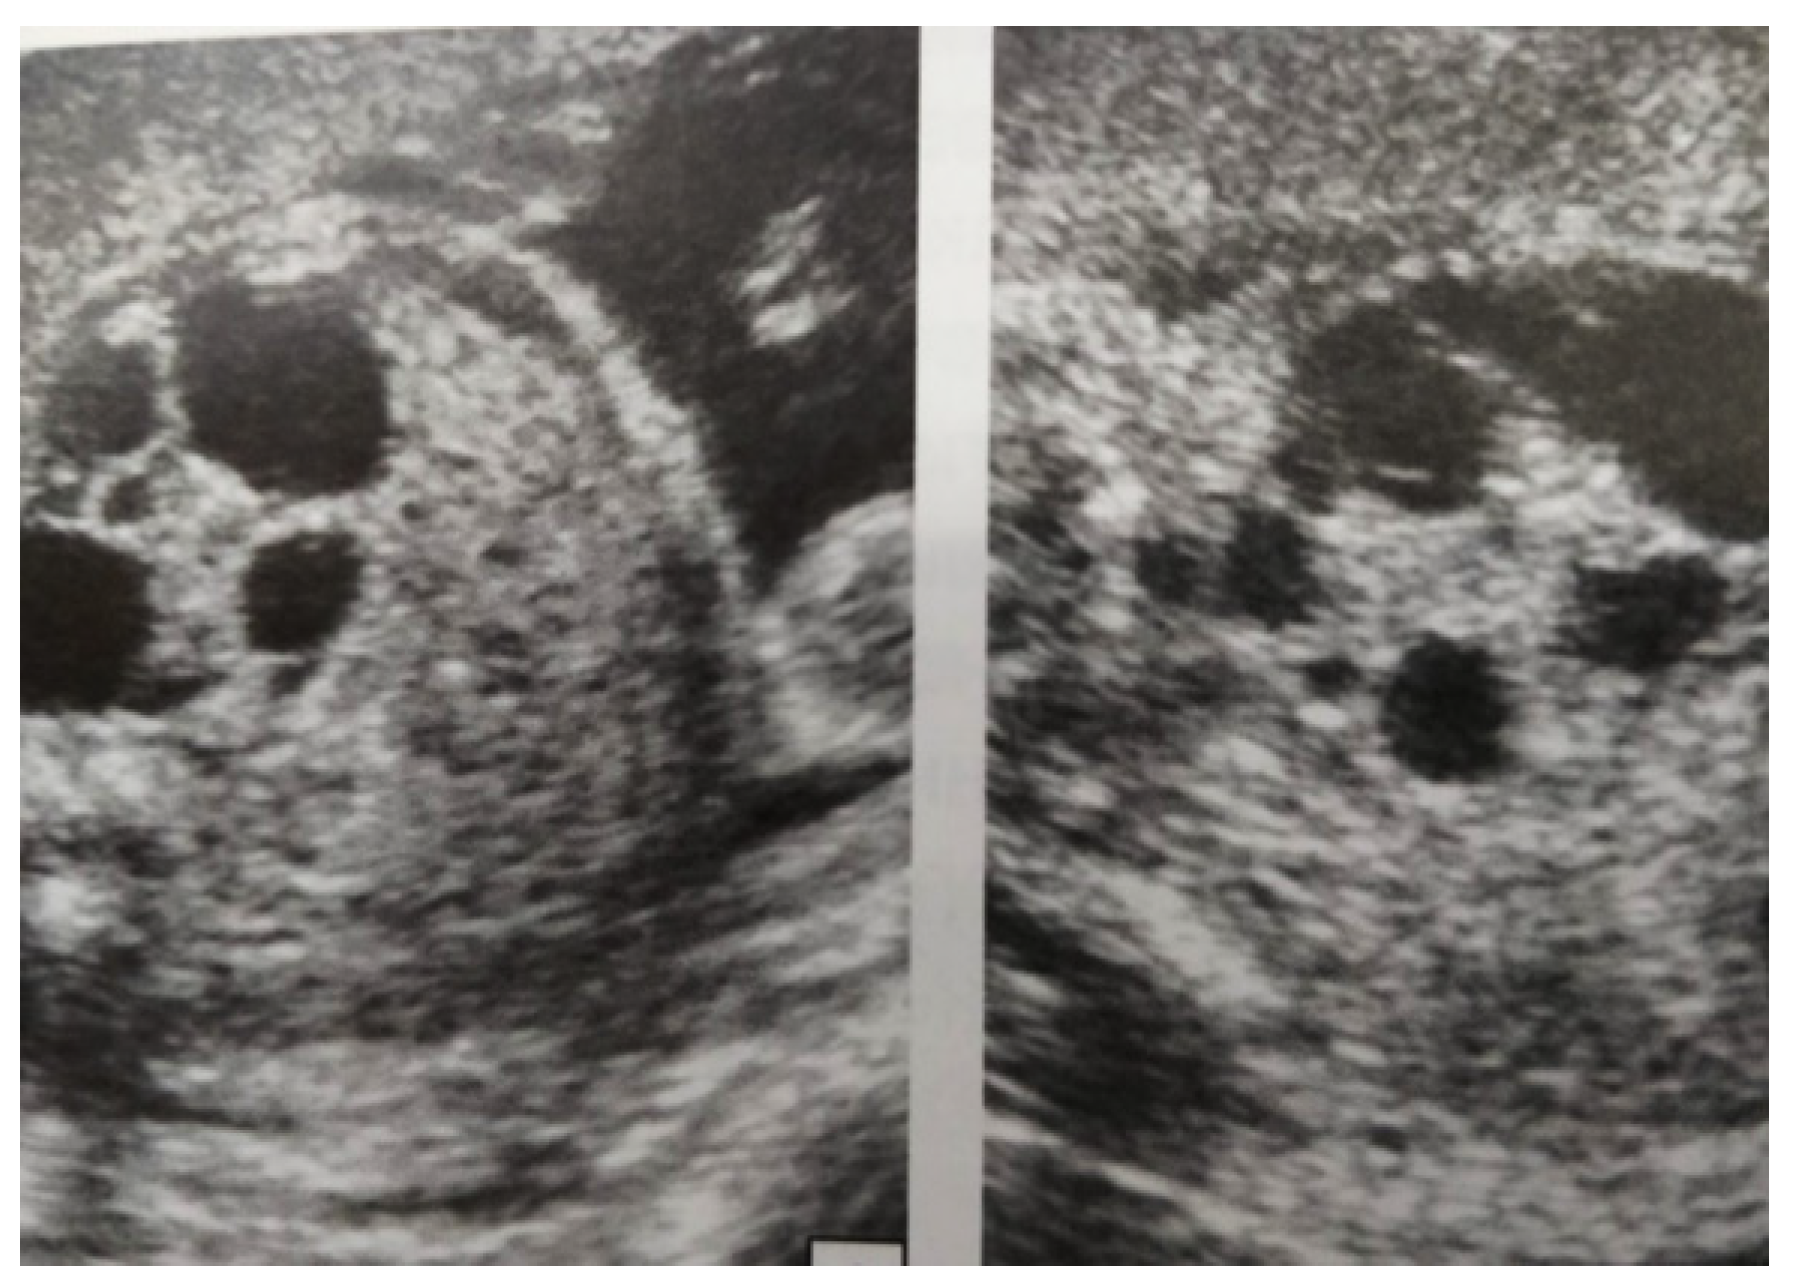

Our experience with congenital malformations of the urinary system refers to the following clinical case (Figure 2, Figure 3, Figure 4, Figure 5, Figure 6, Figure 7, Figure 8 and Figure 9). In the first case, during pregnancy, the 21-week ultrasound determined bilateral renal pyelectasia. The fetus had hydronephrosis on the right; at 31 weeks, it had bilateral hydrocalconephrosis; and at 32 weeks, bilateral pyelectasia. It suffered premature birth at 36 weeks, with complicated anomalies of the forces of contraction, prolonged birth, and birth weight of 2200 g. Postnatal ultrasonography was supplemented by intravenous urography, and bilateral hydronephrosis was determined. Hydrocalconephrosis on the left was discovered. The complete diagnosis was established: congenital renal malformation; bilateral pyelectasia; bilateral hydronephrosis; hydrocalconephrosis on the left; and severe reduced glomerular filtration rate (GFR), GFR > 2SD below mean.

Figure 2. Intrauterine ultrasound at the 21st week of pregnancy. Ultrasonography—the fetus corresponds to the age of 20–21 weeks. Bilateral renal pyelectasia.

Figure 3. Ultrasound at the 20th week of gestation. Hydronephrosis on the right. (1) Dilated pelvis on the right. (2) Uninjured renal parenchyma on the left.